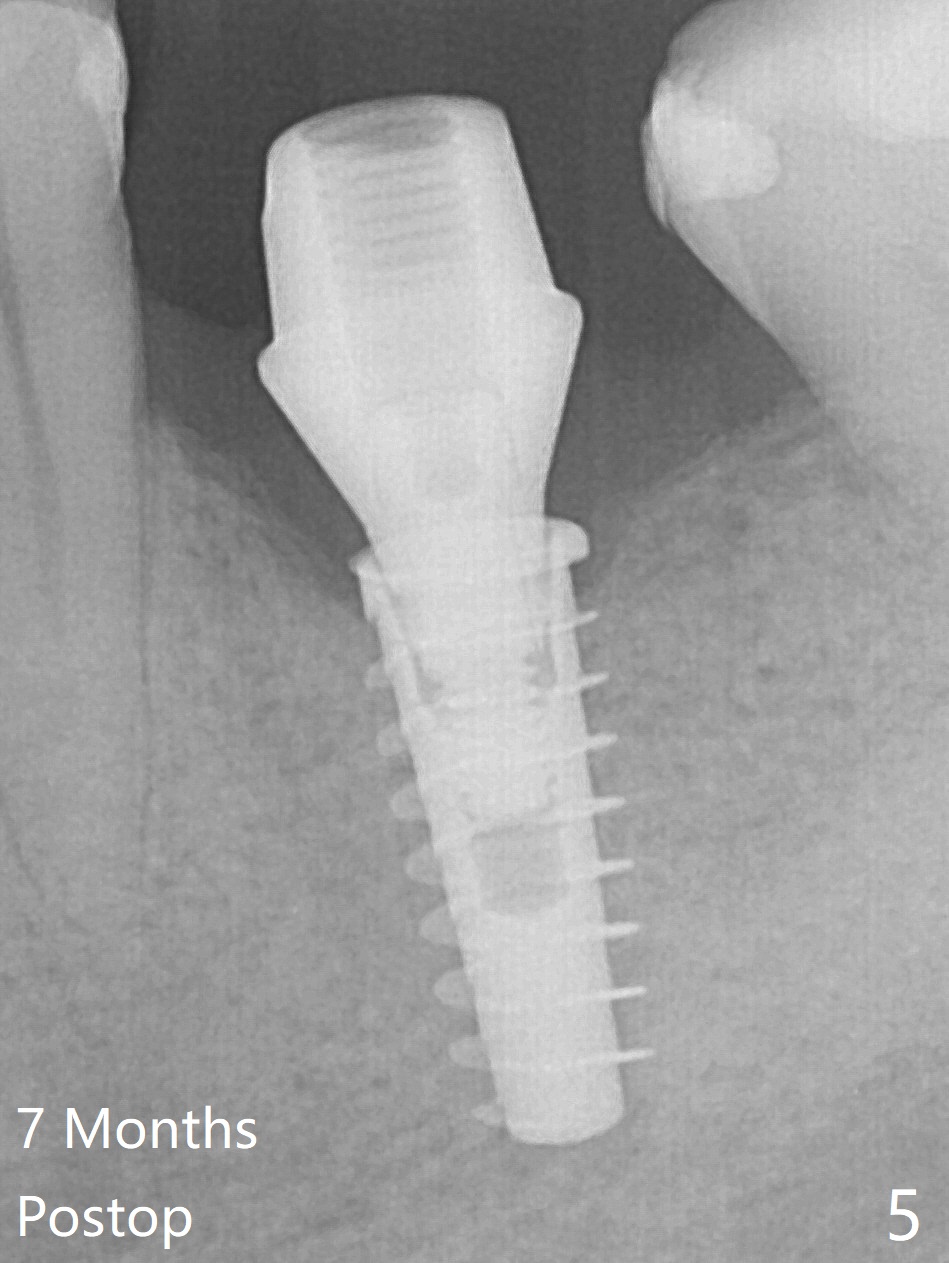

While the mesial ridge is relatively wide associated with residual root at #19 (Fig.1 <), the distal one is narrow (*). Osteotomy is initiated distal to the mesial socket (Fig.2,3 *). Due to the narrow ridge, a 4.5x11 mm implant is placed (Fig.4); before as well as after placement of a 6x4(3) mm abutment, the mesial socket (*) is filled with Vera graft and autogenous bone as well as collagen plug. Following suturing, periodontal dressing is applied to the wound. There is no apparent bone loss 7 months postop (Fig.5,6) or 14 months post cementation (Fig.7). In fact the abutment has been incompletely seated (Fig.5-8), which may be related to #13 failure. The ridge appears to be narrow for the 4.5 mm implant 1.5 years post cementation (Fig.9). When a lady looks skinny with sign of the narrow ridge, choose an implant as narrow as possible.